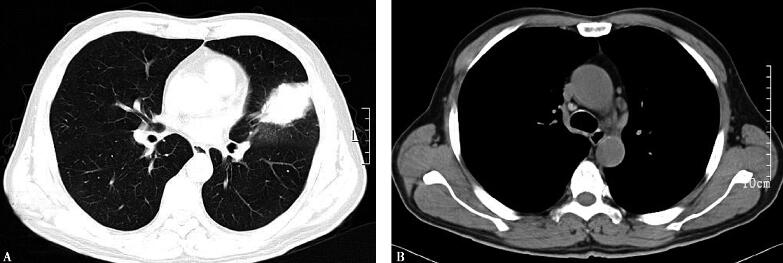

纤维支气管镜下所见:气管隆嵴锐利,左、右肺各叶、段、亚段均未见异常改变(图2),于左舌叶支气管行经支气管壁透壁肺活检技术(TBLB),病理回报:送检组织内有较多淋巴浆细胞浸润,有纤维组织增生,结合临床。

图2

根据肺活体组织病理,考虑为肺部感染性疾病,结合其治疗经过,需要调整抗生素继续抗感染治疗。

治疗1周后,咳嗽、咳痰减轻,仍间断发热,体温波动在37~37.8℃,肺部听诊仍未闻及啰音。复查胸部CT示:左肺上叶舌段病灶未见明显变化,纵隔内淋巴结肿大(图3)。

图3

【临床分析】

患者经积极抗感染治疗后,临床症状有所减轻,但胸部影像学未见明显改变,考虑可能为机化性肺炎,但不能除外肺部恶性肿瘤,可行CT引导下经皮肺穿刺活检或胸腔镜病灶切除。

评价:经过抗生素调整后,该患者体温稍有下降,但是其左肺团块影的性质未明确,肿瘤及隐球菌感染等少见病皆不能除外。由于肺隐球菌感染的痰培养和涂片阳性率一般低于25%,且该患者无宿主妥协因素,无接触鸽粪史等,其最终的诊断只有依靠肺活检。